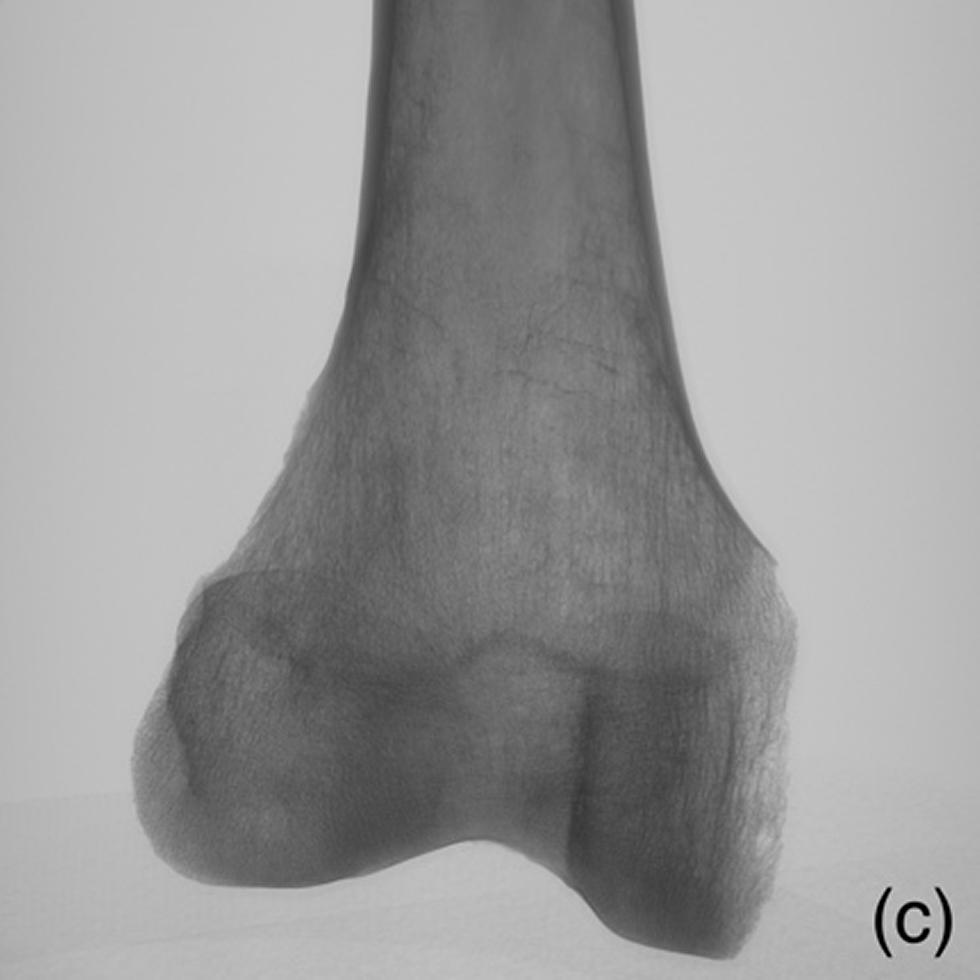

Figures - Example of radiographs acquired during CT scanning for lowest section.

Example of radiographs acquired during CT scanning for lowest section